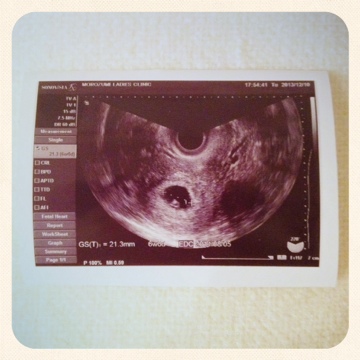

6w1d 心拍 確認-胎嚢確認からちょうど一週間後、心拍確認に行きました。 移植日から見ると6w1d、前回の胎嚢の大きさから行くと6w3dくらいです。 まずは忘れずに、前回渡されていたMedical Recordの公開同意書を提出。 BOGYNに今までの治療歴を送って貰います。 心拍確認も今まで通り経腟エコーで。妊娠週 6w1d 排卵日が特定できているので、確実に6w1dのエコーです (^^)元気な心拍と2mmの赤ちゃんが確認できました! 2人目の妊娠なので、まだ1歳10ヶ月の長男を抱っこしたり追いかけ回したりでゆっくりできないので、赤ちゃんが心配ですが生命力を信じて

体外受精で5w0dに胎嚢(8mm)確認出来てます。 本日6w1d。胎嚢14mm。胎芽2mm。心拍確認済(エコーで拡大して分かる程度) 先生に「赤ちゃん小さいな〜〜」とボソリと言われました。 また、妊娠判定日がBT11でHCG500半ば。 6w1d 心拍確認出来ませんでした 不安になってしまい、また質問させて下さい。 今までの経過は 4w2d胎嚢2mm確認 5w1d胎嚢8mm確認 6w1d胎嚢199mmと卵黄嚢確認 となっています。 ちなみに週数は最終生理から数えてで、医師から告げられたものではありません。 心拍は何週目に確認できましたか? 妊娠初期の妊娠の大まかな目安は8週までに胎児心拍が認められることです。 そのため、 妊娠検薬で早めに妊娠がわかったとしても、 その後心拍確認まで何度も病院に足を運ぶことになります。 およそ1週間ごとに診察

6W1d 胎嚢確認 こんにちは。 今日で6w1dです。 今回も大学病院で。 ということで、朝一番に行ってみてもらいました。 6w1dは、早い人で心拍確認ができる時期なんだとか。 そんな期待と不安を元に行ってきました。 まずは、お小水、血圧、体重と測定しBT24(6w1d)心拍確認① 山場です、山場。 ていうか、この私が心拍確認ドキドキとかなるのが信じられない。 つわりもないし、いろんな覚悟もしつつ内診台へ。 前回、三日月系だった胎嚢がまん丸に。(私にはそう見えた)6w1d 22日、判定日から2回目6w1dでの診察でした。 先週先生に6wで心拍見えると思いますのでと言われていたので、それからと言うもの日々心拍について調べてしまう私 (>_